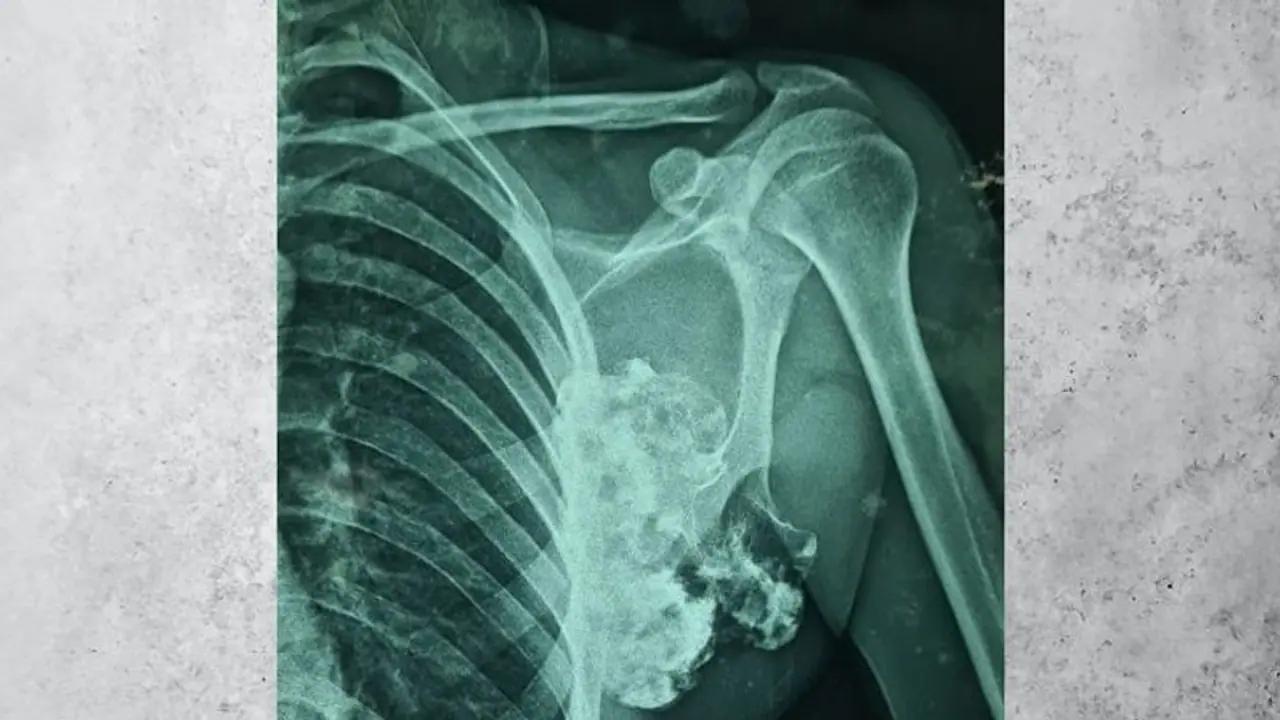

एक्सरे रिपोर्ट देखकर सन्न रह गए डॉक्टर

डॉक्टरों ने जब युवक की एक्सरे जांच कराई तब उसकी हालत देखकर एक बार तो डॉक्टर भी दंग रह गए । बाद में सभी डॉक्टर ने मीटिंग की और इस मीटिंग में ऑपरेशन करने की तैयारी शुरू की गई। ऑपरेशन डॉक्टर जोशी के मार्गदर्शन में डॉक्टर राकेश एवं डॉ विशाल शेखावत की टीम ने किया । डॉक्टर्स की टीम ने बताया कि जो ट्यूमर कंधे की स्कैपुला हड्डी के पास से निकाला गया है । वह दुनिया में प्रकाशित जर्नल्स में स्कैपुला हड्डी की निकाली गई अब तक की सबसे बड़ी ट्यूमर है।